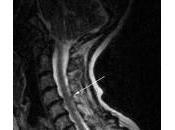

Tratamiento Endoscopico de las Hernias Discales

De todas las discopatías, solo un 10% requieren de cirugía para extraer la hernia y compensar esa rotura de anillo que irrita la raíz y provoca las molestias. Leer el resto